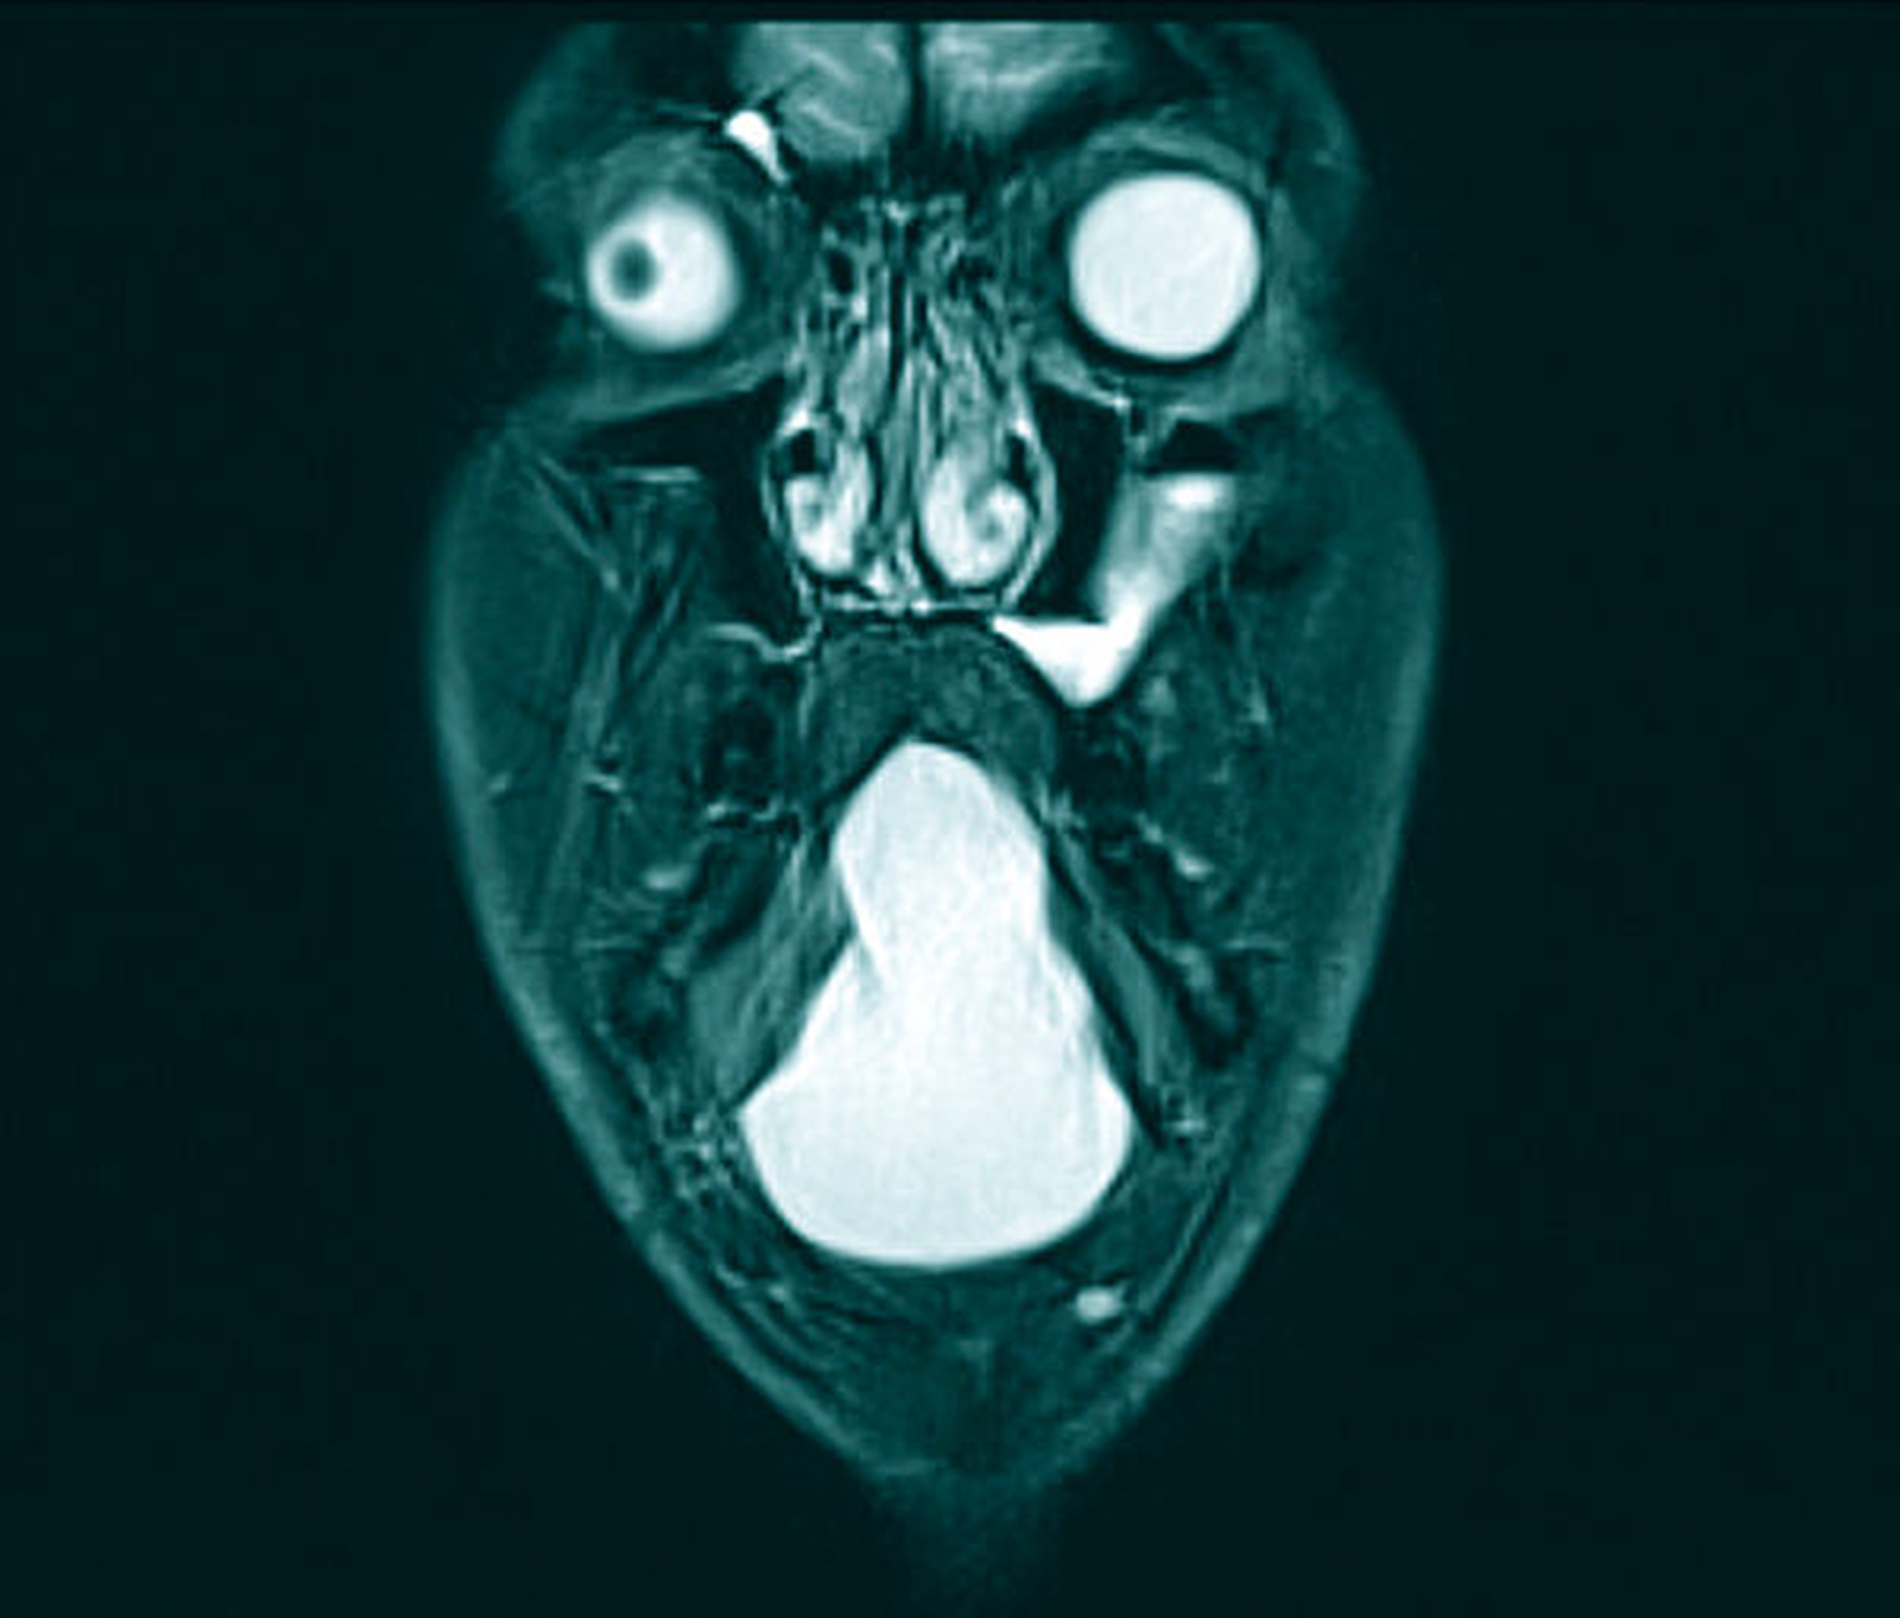

Zur Diagnostik erfolgten eine Sonografie sowie eine Magnetresonanztomografie des Halses. Hierbei kamen zwei voneinander getrennte zystische Raumforderungen submental und im Bereich des Mundbodens zur Darstellung: Die submentale Raumforderung mit einer Größe von maximal 3,5 cm war direkt zwischen der Hautoberfläche und dem M. mylohyoideus, dem Unterkieferknochen angrenzend, lokalisiert. Die zweite Raumforderung mit einer Größe von 6,5 cm erstreckte sich großflächig entlang des gesamten Mundbodens, oberhalb des M. mylohyoideus, mit resultierender Verdrängung der tiefen Zungenmuskulatur und des Zungenkörpers sowie direkter Nachbarschaft zum Ausführungsgang und der Glandula submandibularis beidseitig und ohne Kontakt zum Zungenbein (Abbildungen 3 bis 5).